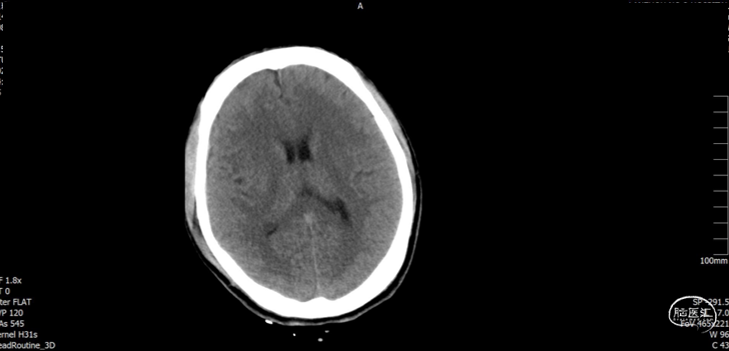

入院检查

![]()

入院化验

积极纠正凝血功能:氨甲环酸1g